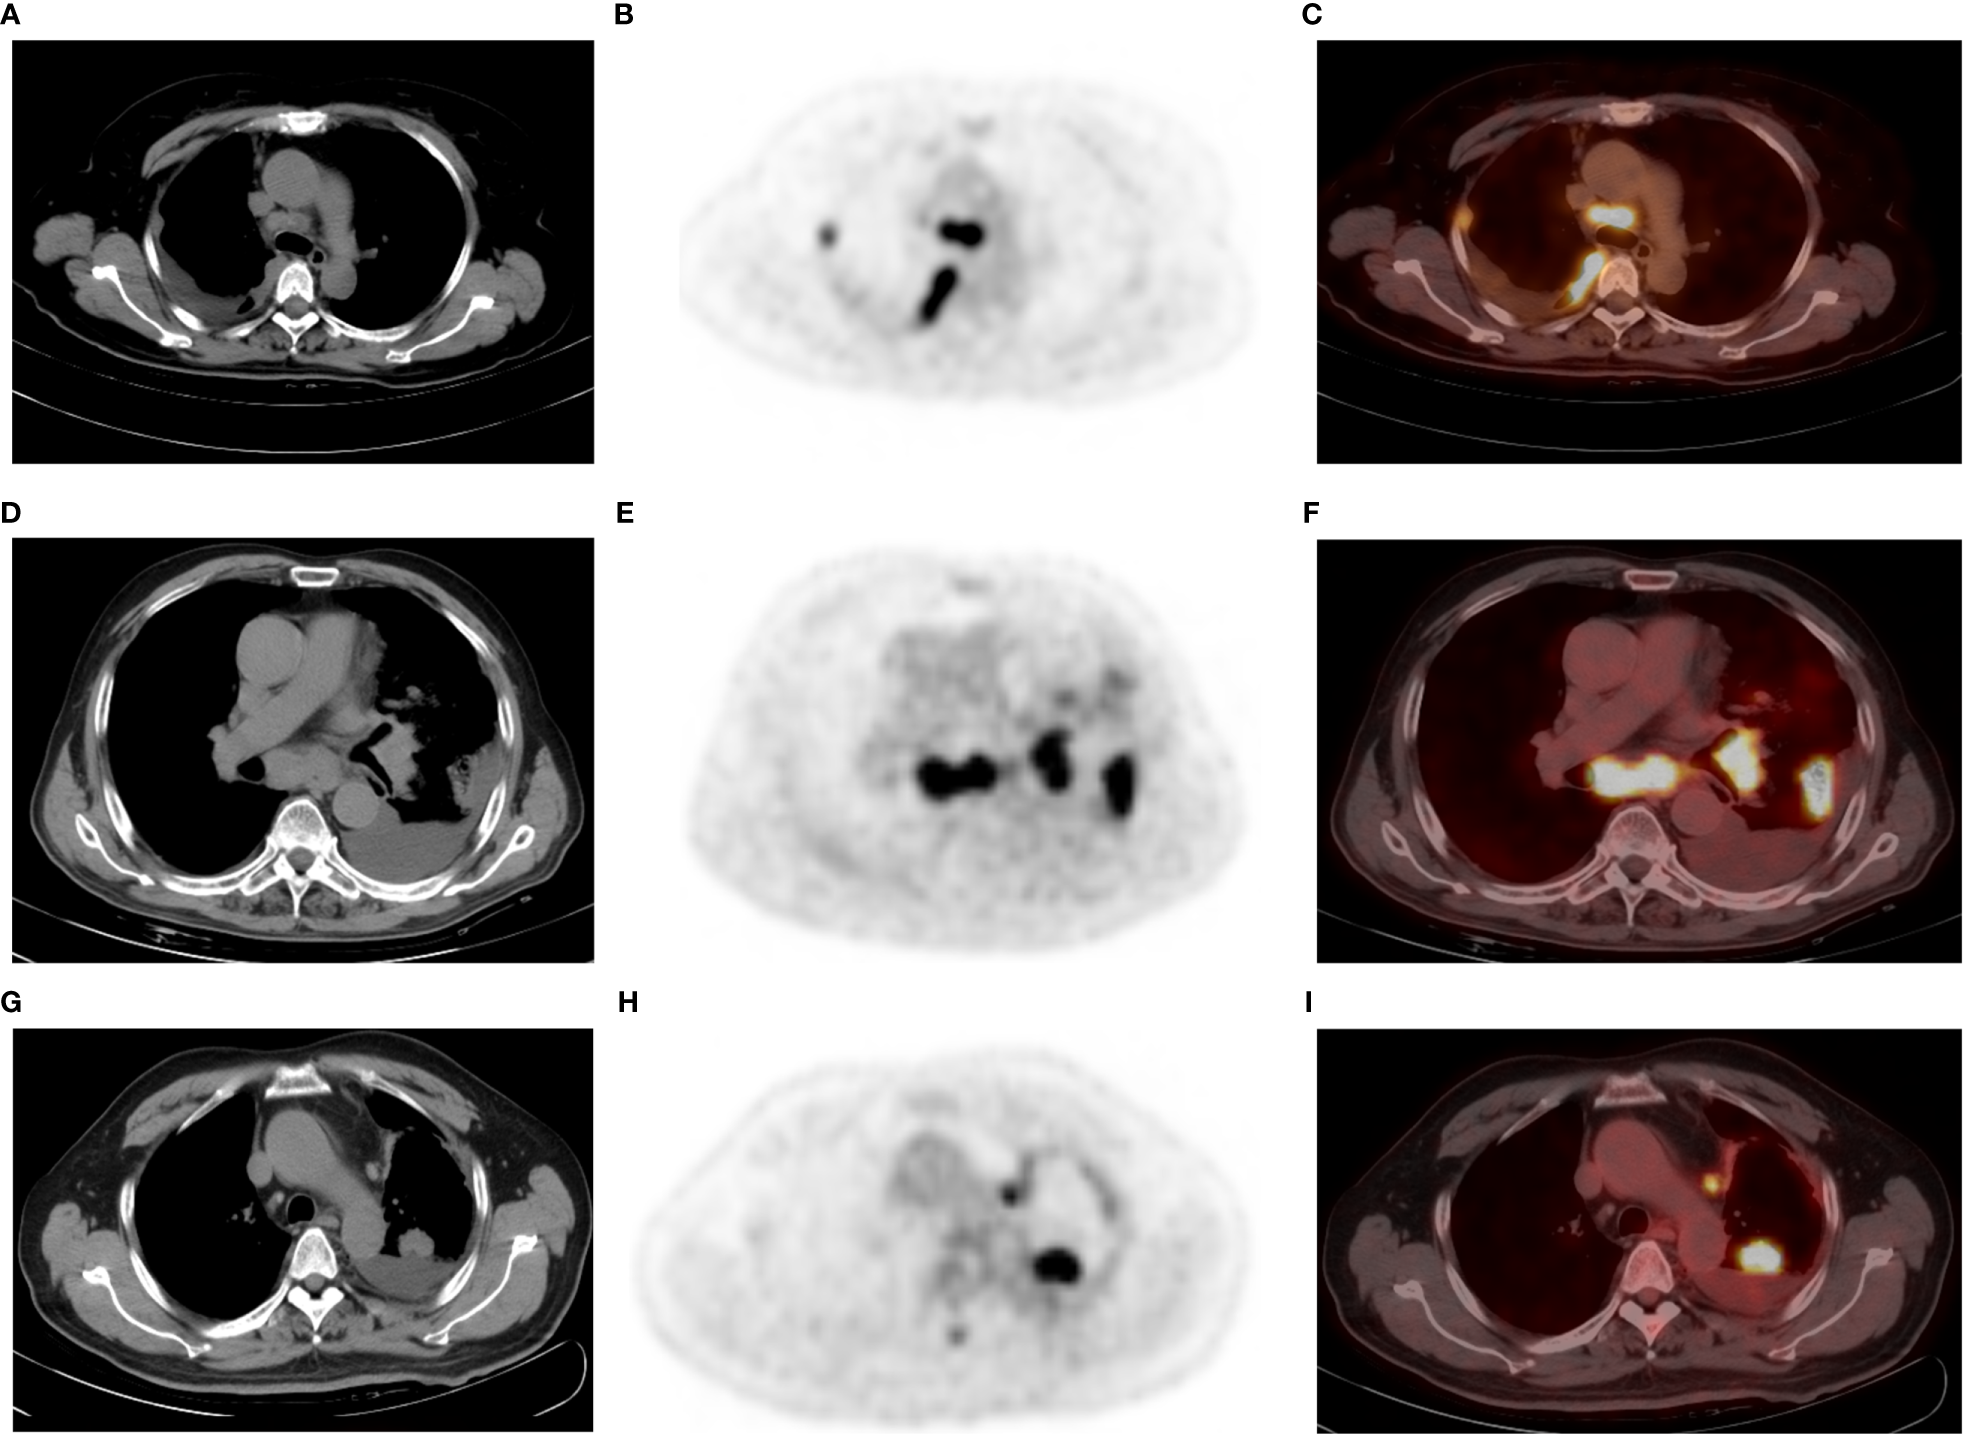

Figure 2

A 52-year-old man with poorly differentiated lung adenocarcinoma and right-sided malignant pleural effusion (A–C). Axial CT (A) revealing effusion in the right pleural cavity, and axial 18F-FDG PET (B) and fused PET/CT (C) revealing nodular 18F-FDG uptake (SUVmax 4.4) in the same pleural region. Thoracentesis-based pathology confirmed MPE caused by metastatic adenocarcinoma. A 77-year-old man with lung adenocarcinoma and left-sided BPE (D–F). Pleural fluid cytologic findings were negative, without recurrence of pleural abnormalities on follow-up. Axial CT (D) revealing a left peripheral lung cancer with left pleural effusion, as well as pneumonia, mediastinal, and left hilar lymphadenopathy. Axial PET (E) and fused PET/CT (F) revealing hypermetabolic areas in the tumors without abnormal FDG uptake in the pleura. A 65-year-old man with left lung adenocarcinoma and left-sided MPE (G–I), who did not have an enlarged lymph node in the mediastinum or hilar region. Axial CT (G), PET (H) and fused PET/CT (I) revealing a left PE, lung mass (SUVmax: 13.9), and mediastinal pleural thickening (thickness: 5.6 mm and SUVmax: 4.1). PE cytology confirmed MPE. Note that the largest thoracic lymph node of this patient is located next to the aortic arch with a short diameter of 7 mm and SUVmax 6.5.